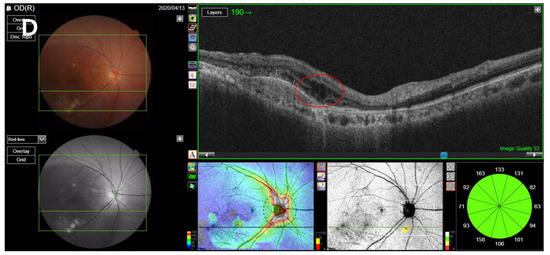

SS-OCT was performed on the enrolled eyes of all included patients using a swept-source DRI OCT Triton Plus (Topcon Co., Tokyo, Japan) at each follow-up point. Using the OCT scans, we recorded the central subfield thickness (CST) and any anatomical abnormalities including accumulated levels of subretinal fluid (SRF), intraretinal fluid (IRF), and subretinal hyperreflective material (SHRM) and presence of pigment epithelial detachment (PED), and measured the maximum height of the SRF and PED. CST, which refers to the average retinal thickness within a 1-mm-diameter ring based on the macula [19], was measured using built-in optical software (IMAGEnet 6 version 1.25.16650; Topcon Co., Tokyo, Japan). Anatomical abnormalities in OCT images, such as the levels of SHRM, SRF, PED, and IRF, were found to indicate exudative disease activity [20,21,22]. For patients with confirmed SRF accumulation or PED, the maximum SRF height (distance between the outer retina and the hyperreflective line of the RPE) was manually measured using the caliper tool in IMAGEnet software; a similar process was repeated to measure the maximum PED height (distance between the inner surface of the Bruch membrane and the outer surface of the RPE) by reviewing the OCT image [23,24] (Figure 1).

Figure 1.

Measurement of SRF, PED, SHRM, and IRF. (A) The maximum SRF height was measured as the maximum distance between the outer retina and the hyperreflective line of the retinal pigment epithelium on the OCT image, using the caliper tool using IMAGEnet software. (B) The maximum PED height was measured as the maximum distance between the inner surface of the Bruch membrane and the outer surface of the retinal pigment epithelium. (C) Presence of SHRM, which is a morphological feature seen on OCT as hyperreflective material located external to the retina and internal to the retinal pigment epithelium. (D) Presence of IRF, which appears as dark cystic accumulations of fluid above the outer plexiform layer. SRF, subretinal fluid; PED, pigment epithelial detachment; SHRM, subretinal hyperreflective material; IRF, intraretinal fluid; OCT, optical coherence tomography.